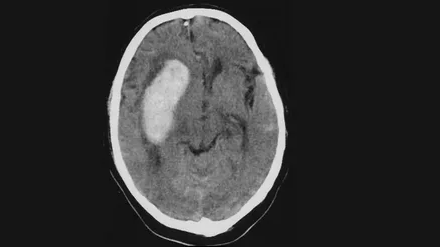

При каком артериальном давлении чаще происходит инсульт?

Почему инсультов больше при умеренно высоком давлении 140–160, чем при очень высоком 180–200 и выше? Интуитивно ведь ожидается обратное, однако данные, основанные на больших выборках, показывают иную картину. Дело в том, что риск инсульта растет непрерывно с повышением уровня артериального давления, причем без какого-либо порогового уровня, за которым начинался бы скачкообразный рост. При этом людей с показателями 140–160 мм многократно больше, чем с АД 180–200 мм, поэтому именно в таком диапазоне...